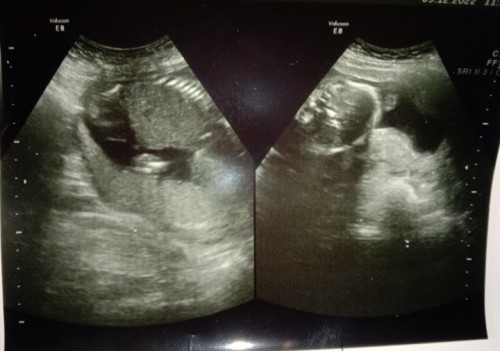

ใครดูภาพอัตราซาวด์เป็นบ้าง ช่วยดูให้หน่อยค่ะ น้องเป็น ชาย รึ หญิง คะ ขอบคุณล่วงหน้าค่ะ น้อง 19 w น้ำหนัก 240gค่ะ